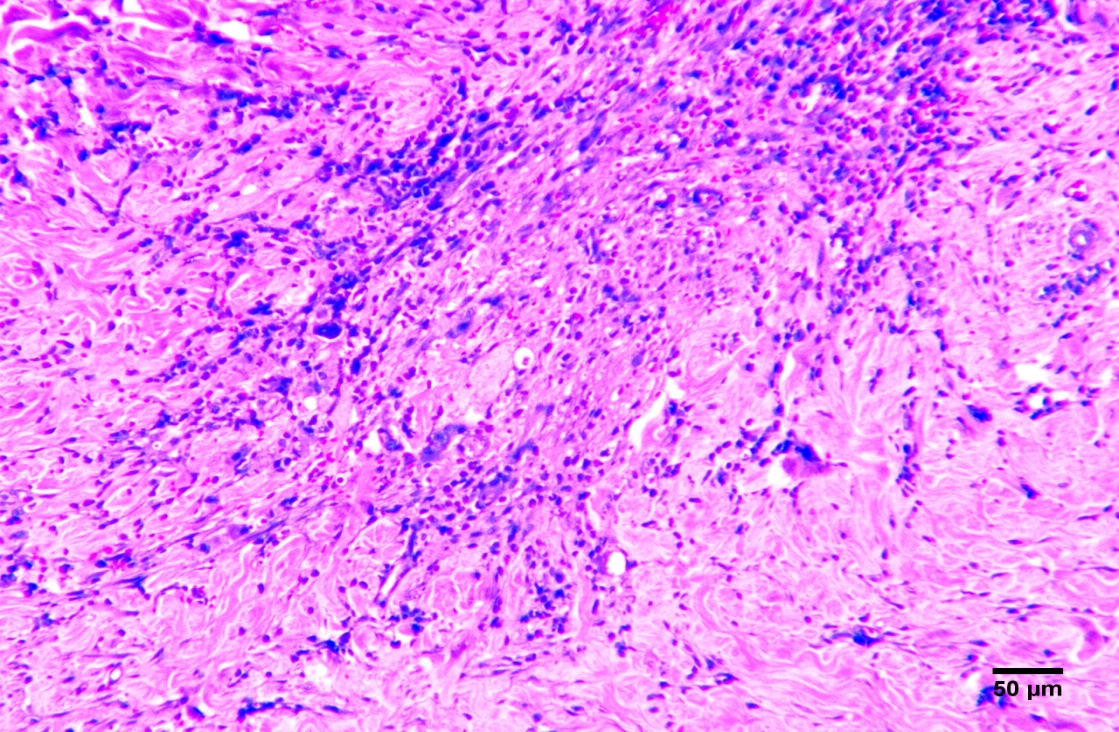

O presente estudo teve por objetivo desenvolver e investigar experimentalmente as potencialidades de aplicação de bioadesivo a base de amido aditivado, como sistema patches transdérmico e intradérmico epitelial, em formato de filme monolaminar tubular, visando à ação futura para administração de anti-inflamatórios, antimicrobianos e atuação terapêutica. Foram utilizados 20 coelhos machos e fêmeas, da raça Nova Zelândia, adultos, separados em quatro grupos com cinco animais que passaram por cirurgia para realização de defeito dérmico. O grupo GA e o grupo GB (controle dérmico e intradérmico negativos respectivamente) não receberam biomaterial na ferida. Os animais do grupo GC receberam o biofilme adesivo de forma dérmica que foi suturado sobre a ferida e o grupo GD, recebeu o biofilme adesivo de forma intradérmica. Aos sete e 14 dias de pós-operatório os animais foram anestesiados novamente para criação do defeito para biópsia. A análise estatística da planimetria foi conduzida a partir da média dos grupos, utilizando-se o teste de Tukey a significância de 1%, através do software computacional estatístico SAS®. A pesquisa demonstrou que o biofilme utilizado até sete dias reduz o processo inflamatório e estimula a neoangiogênse.